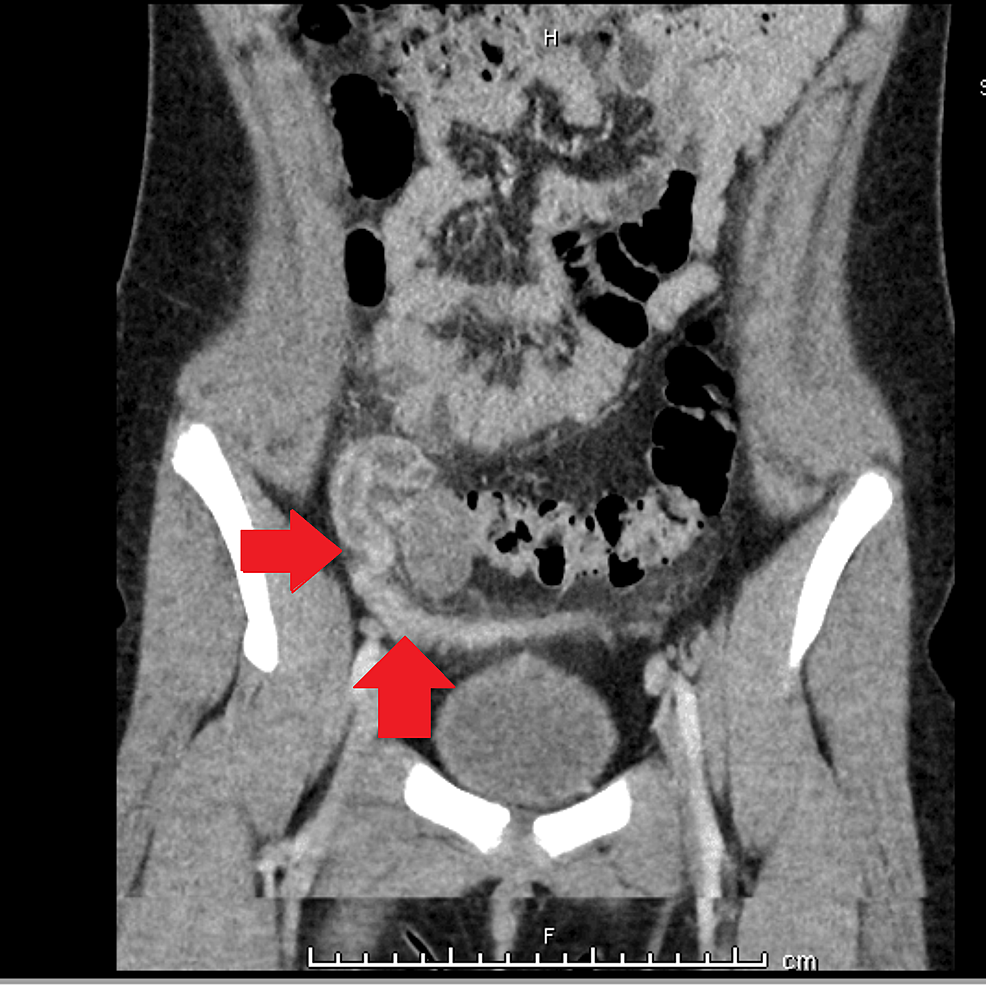

Cureus The Role of a Spinning Top Urethra in the Development of Pyosalpinx in a Precoital Female

From www.cureus.com

Cureus The Role of a Spinning Top Urethra in the Development of Pyosalpinx in a Precoital Female Spinning Top Urethra Mean 2b) , characterized by dilation of the. the mean voiding pressure was measured as 56 ± 29 cmh 2 o in group i, which was significantly higher than in group ii (49 ± 25 cmh 2 o). spinning top urethra is a rare deformity, characterized by dilated posterior urethra, more common in young women. an anteroposterior image. Spinning Top Urethra Mean.